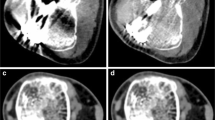

One drawback of advanced and hybrid metal artifact reduction techniques is the often long scan time. Two main approaches have been investigated to overcome this problem (Figs. 5 and 6). Compressed sensing (CS) has been used to accelerate SEMAC acquisition and demonstrated feasibility for imaging of total hip prosthesis and other anatomic regions, and for the differentiation between normal postoperative MRI findings and abnormal findings after total hip prosthesis [61,62,63,64]. The combination of CS and SEMAC has been shown to reduce acquisition times to 5–6 min for hip prostheses, allowing it to be incorporated easily into routine imaging protocols. At the same time, image quality is improved compared to standard SEMAC pulse sequences because of the increased number of slice-encoding steps. In addition, its high accuracy in detecting periprosthetic pathologies, such as infections, makes it a reliable sequence for assessing periprosthetic complications of large implants [50, 65, 66]. For MAVRIC imaging near metal implants, a short spectral calibration scan of about 35 s can be used for optimizing the number of spectral bins to minimize susceptibility effects and reduce scan time [17, 67]. For the combined MAVRIC-SL sequence, this calibration scan allowed to achieve scan times of 5–6 min for conventional acquisitions of hip prostheses compared to more than 8 min for MAVRIC imaging alone, and with an additional decrease of the repetition time an isotropic MAVRIC-SL was possible in 7:16 min with improved SNR [56] (Table 5).

1.5-T MRI of the right hip of a 57-year-old patient 1.5 years after total hip arthroplasty. The radiograph shows a normal position of the implant made of titanium alloy (A). However, the coronal short-tau inversion recovery (STIR) turbo spin echo sequence (B) combined with compressed sensing (CS) and slice encoding for metal artifact correction (SEMAC) shows severe joint inflammation with increased synovial fluid, extensive bone marrow edema (arrowhead and outline arrow), and strongly hyperintense signal of the surrounding soft tissues (arrow); this imaging pattern is highly suspicious of a periprosthetic joint infection. The axial short-tau inversion recovery (STIR) turbo spin echo sequence (C) with optimized inversion pulse (STIR WARP) shows abscess collections within the anterior surgical access route. Joint aspiration proved a low-grade infect with Cutibacterium avidum. The images were acquired at 1.5 T with following sequence parameters: STIR SEMAC CS—echo time (TE) 36 ms, repetition time (TR) 4220 ms, receiver bandwidth 500 Hz/pixel, inversion time (IT) 160 ms; STIR WARP—TE 31 ms, TR 4000 ms, receiver bandwidth 450 Hz/pixel, IT 150 ms